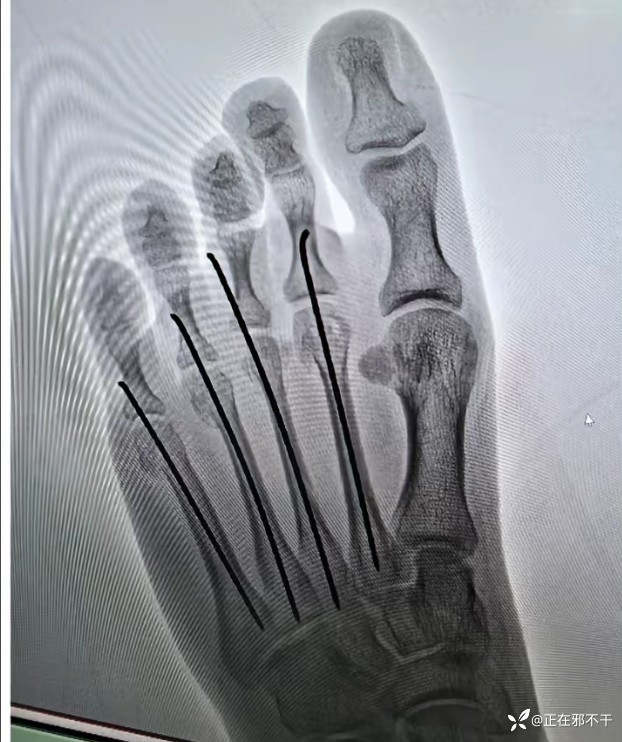

【治疗经过及结果】:给予克氏针闭合复位内固定

这种固定看似简单,做起来是需要技术的。

借助C型臂X射线机的监视与诱导,能够实现精确的解剖复位。此手术方式微创且无手术切口,从而显著减少甚至规避患者并发感染的风险。其稳定性亦相当出色,能够有效预防医源性的神经损伤,进而降低并发症的发生率。更为重要的是,它还能加速骨折的愈合进程,为患者节省医疗费用。